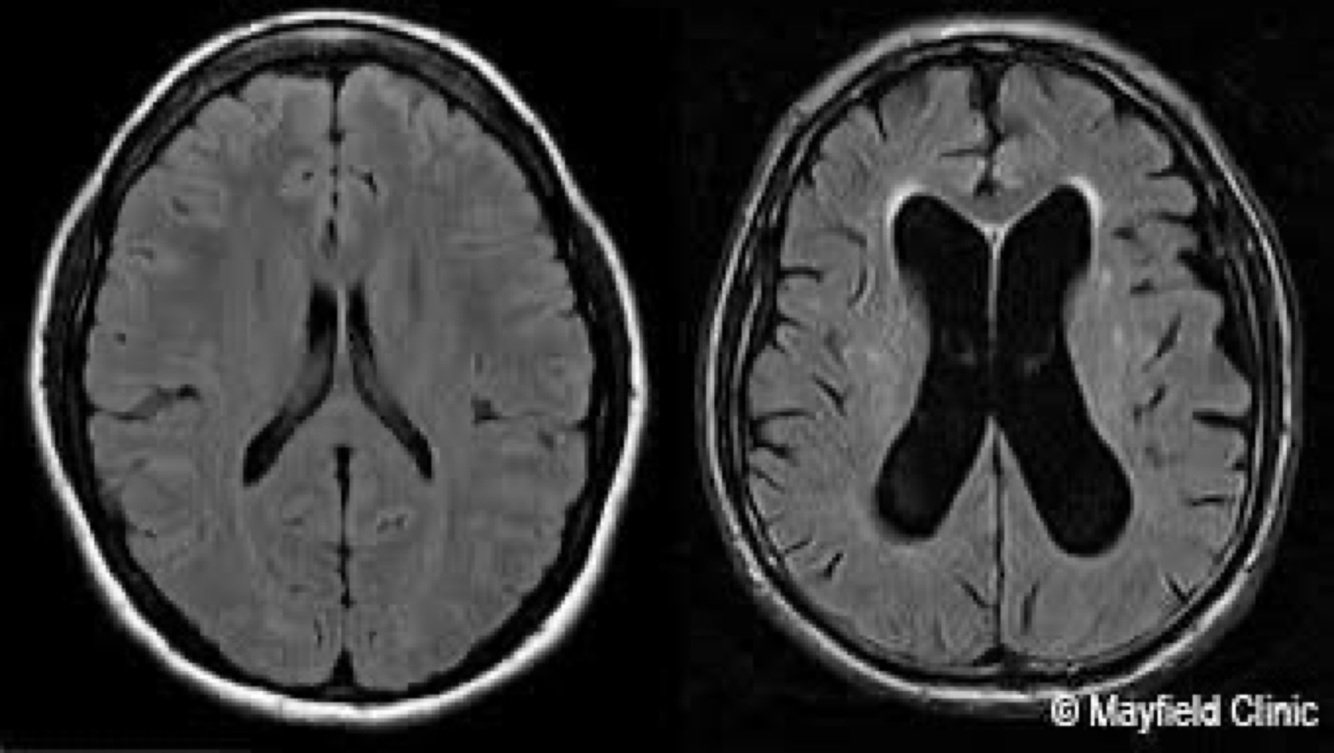

Imaging Findings

• CT/MRI:

- Caudate nucleus atrophy → enlarged frontal horns of lateral ventricles (classic exam question)

- Cortical atrophy in advanced disease

• Caudate atrophy = hallmark (think “C for Caudate = C for Chorea”)